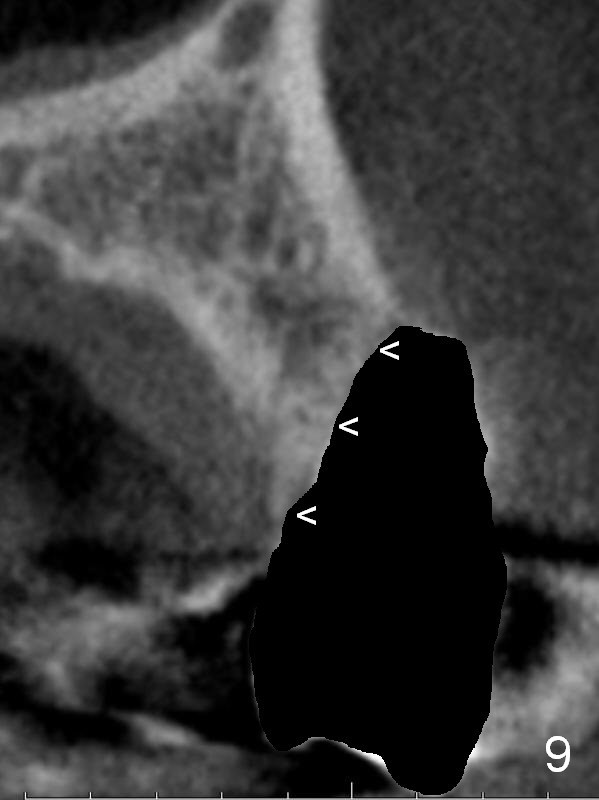

After extraction, the bottom of the socket must be oblique (Fig.9 arrowheads). As usual, osteotomy is initially at the junction of palatal (Fig.10 P) 1/3 and middle 1/3 perpendicular to the plate.  Once the drill gets engaged, the trajectory is to be changed (Fig.11 curved arrow) so that the apical end of the osteotomy (red line) is as close to the buccal plate (B) as possible.  The purpose is to keep the palatal end of the osteotomy as palatal as possible.  In spite of the effort, an angled abutment is expected, as large as 20 degree (Fig.8 purple angle).